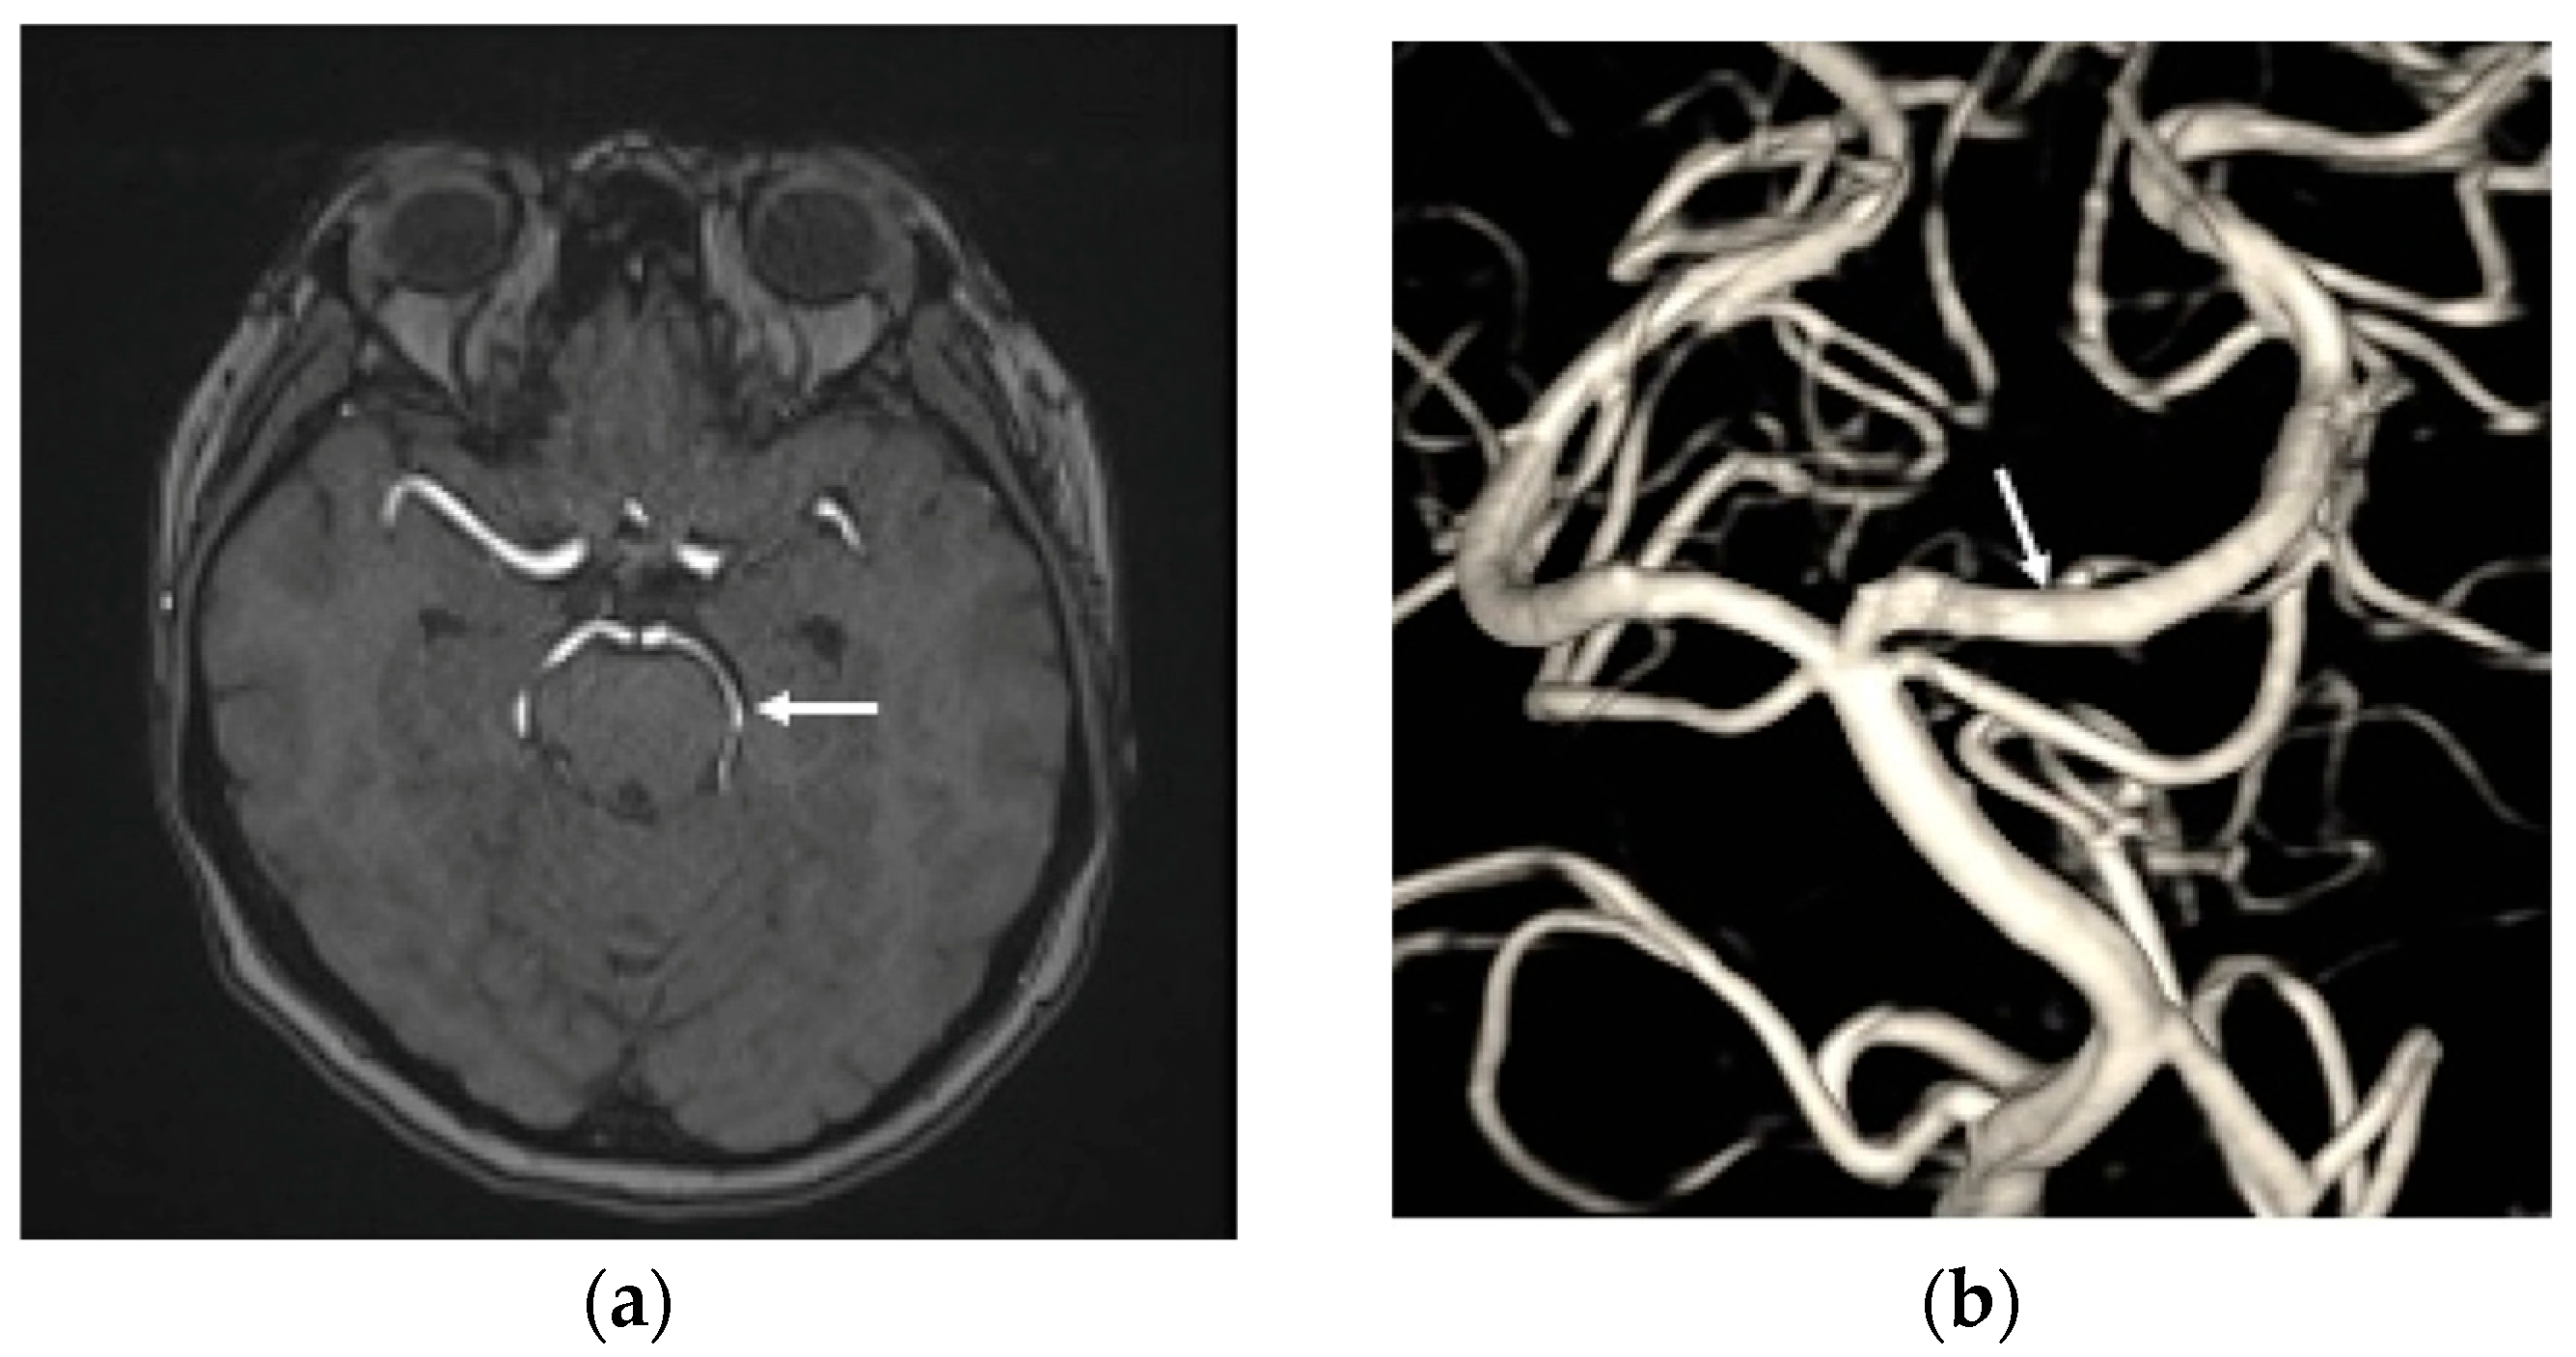

2. Case Report